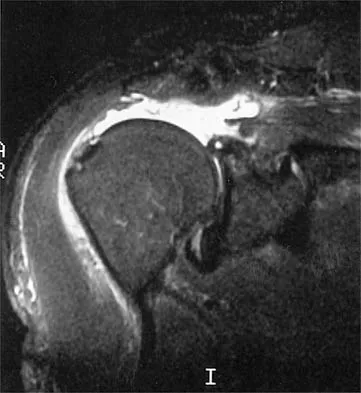

Question 43

An 80-year-old man has had increasing shoulder pain for the past 4 months. He reports that it began with soreness and stiffness after chopping some wood. A coronal MRI scan is shown in Figure 16. Initial management should consist of

Explanation